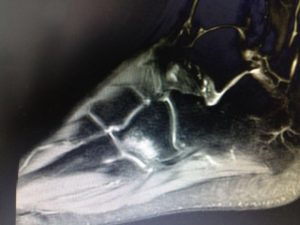

El tendón de Aquiles es la estructura terminal del tríceps sural. Formado por los músculos sóleo y gemelo medial y lateral, se encarga de transmitir la potencia flexora al antepié sobre el hueso calcá [...]

La tendinitis aquílea es una condición en la que el tendón que une la parte trasera de la pierna con el talón se inflama y causa dolor en la zona cercana a la base del pie. Este tendón, conocido como [...]